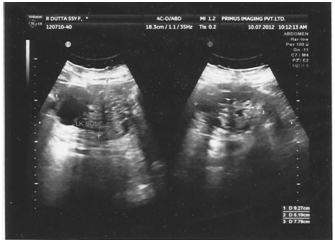

A 53years old obese woman presented with vague abdominal pain of one year duration. Physical examination was unremarkable. Ultra sonography of the whole abdomen detected an exophytic complex cystic lesion measuring about 10x8cm in upper pole of left kidney (Figure 1). MDCT whole abdomen showed 9.4x7.7x7.5cm sized multiloculated cystic lesion with enhancing septae and calcifications with solid nodular areas (Figure 2). The patient was diagnosed as Stage II left Renal Cell Carcinoma and subjected to Radical Nephrectomy. Adrenal was also removed as the tumor was in upper pole. On gross examination the tumour was multi nodular. Cut surface shows a spongy mass measuring 11x8.5x5cm, filled with yellowish serous fluid in the upper pole. On microscopic examination, the tumour was composed of variably sized tubules and fenestrated channels lined by bland cuboidal cells to epithelioid cells. No mitosis, cytological atypia, or nuclear pleomorphism was seen. Remaining kidney showed patchy chronic pyelonephritis with glomerulosclerosis and scarring. The adrenal showed normal histological appearance. Histopathology of the tumor was suggestive of Adenomatoid tumor of kidney (Figure 3). The tumor was positive for vimentin on immunohistochemistry.

Figure 1 Exophytic complex cystic lesion (10x8 cm) in upper pole of left kidney.